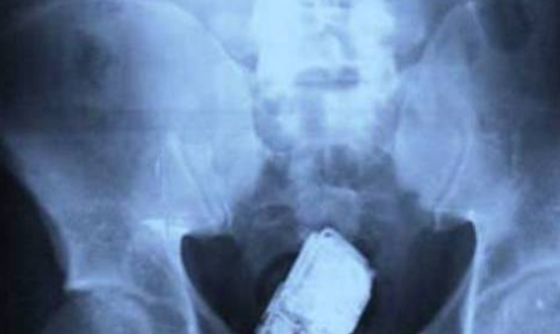

7、手机

x光片发现十大最恐怖的东西,你绝对想不到居然有它981 / 作者:UFO外星人爱好者 / 帖子ID:47859

在圣萨尔瓦多的一所监狱里,结肠内的手机表明了一些人为了保持联系而愿意忍受非人一般的疼痛。